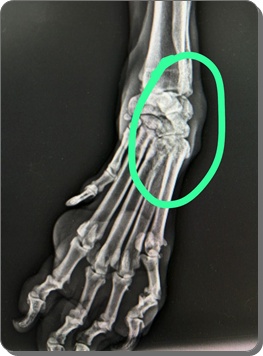

In der Röntgenuntersuchung der Gliedmaßen wurden Veränderungen festgestellt,

die auf eine beginnende Osteoporose hinweisen, sodass die Knochenstruktur

als nicht gesund bewertet wird und eine erhöhte Fragilität

(leichteres Brechen) anzunehmen ist.